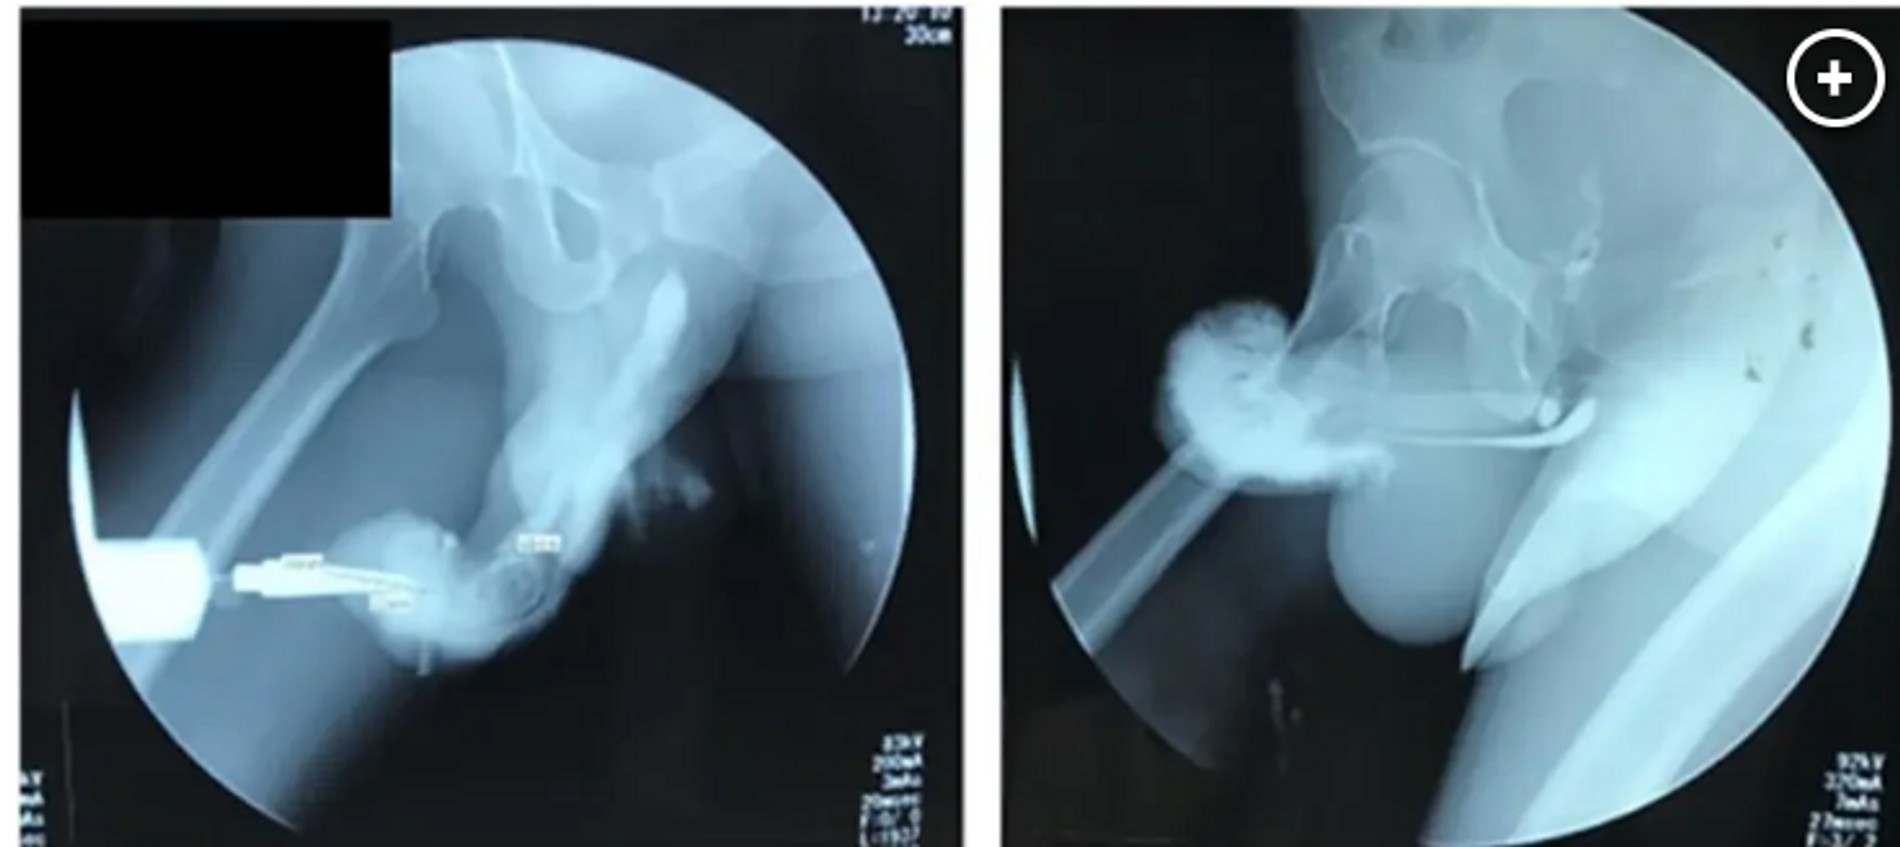

Сообщается, что в роковой момент мужчина внезапно услышал и почувствовал хруст, который сопровождался болью и немедленной потерей эрекции. У горе-любовника началось кровотечение из кончика полового члена. Также он обнаружил, что не может мочиться. К тому моменту, как до смерти перепуганный индонезиец обратился к врачу, его член опух и приобрел темно-фиолетовый цвет. Такое состояние в медицине называют баклажановой деформацией.

В публикации в журнале Urology Case Reports специалисты отмечают, что, вообще-то, мужской половой орган технически бескостен, словом «перелом» в данном случае описывают разрыв оболочки — ткани, которая позволяет пенису увеличиваться и подниматься.

После операции, которая прошла успешно, пострадавшему во время секса мужчине на три дня наложили гипс на член. На пятые сутки пациента выписали. Через месяц после операции индонезиец уже мог заниматься сексом. Проблем с эрекцией у него не было.